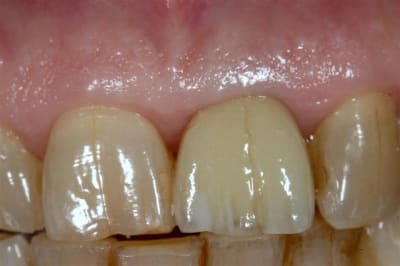

Allez, pour apporter mon caillou à la plage, un cas intéressant, d'implant en urgence.

consultation suite à une chute et fracture de 21 couronnée, un 29 Décembre, décision de poser l'implant le 31.12.

Extraction, mise en place d'un implant de 5*11.5 torque > 35N

Mise en place d'une dent provisoire transvisée.

Prothèse transvisée définitive à 3 mois.

Les 2 dernières photos à 1 an.

la photo ceram en place est à 6 mois. Noter l'amélioration des papilles entre 6 mois et 1 an...

Résultat top Cingulum !

yeaaah! elle est pas belle la vie!

19.5/20 (un peu moins de lemon et un peu plus de red et c'était le 20/20)